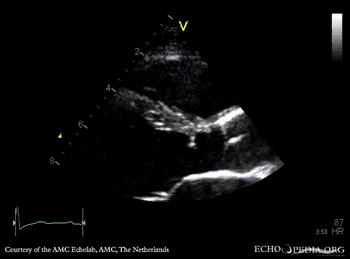

Subvalvular membrane

PSAX: subvalvular membrane PSAX: subvalvular membrane, zoom